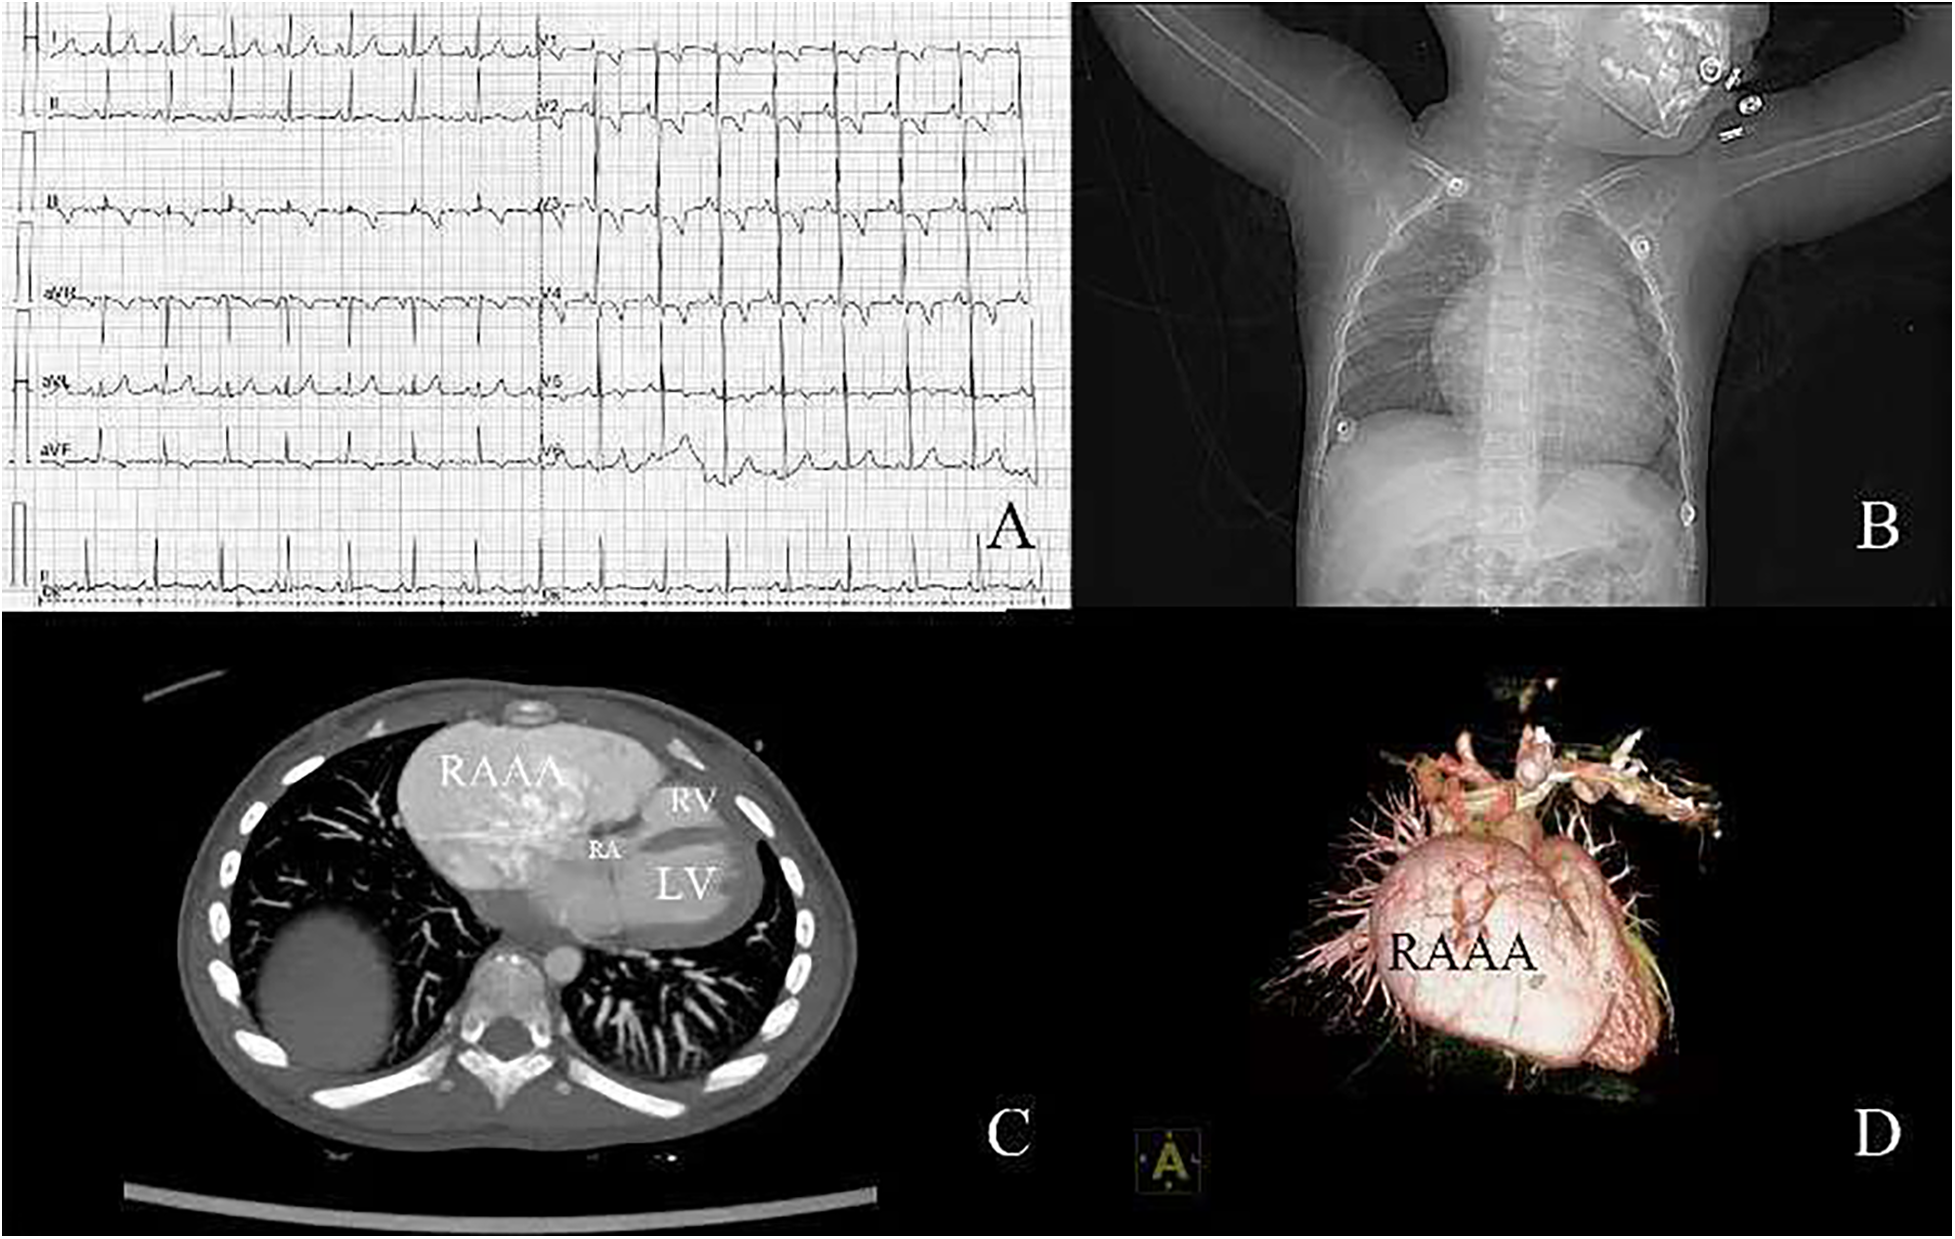

A 2-year-old boy was admitted to our hospital because of an enlargement of cardiac shadow incidentally revealed by chest x-ray during a routine physical examination. According to his parents, the patient had no cardiac symptoms. No heart murmur was found and the electrocardiogram showed sinus rhythm (Figure 1A). The chest x-ray showed an obvious enlargement of heart shadow (Figure 1B). Contrast computed tomography scan and 3D reconstruction demonstrated a giant right atrial outpouching arising from the right atrial appendage. It measured approximately 95 × 43 mm (Figures 1C,D). Though without clinical symptoms and complications, the patient underwent surgery to resect the aneurysm due to its large size and potential impact on function of right atrium, right ventricle and tricuspid valve caused by its compression. The operation was performed under cardiopulmonary bypass. During the surgery a 105 × 55 mm noncontractile cystic structure originating from the right atrial appendage was found locating on the right anterior side of the right atrium (Figures 2A,B). Through the incision upon the surface of the aneurysm, the inner structure of the cystic outpouching, coronary sinus and the inflows of the caval veins were checked (Figure 2C). Except for thinning wall of the aneurysm, no other abnormalities like intracavity thrombus were detected. Along the border between normal atrial wall and thinned aneurysmal wall, the aneurysm was resected. The right atrium and its connection to superior vena cava were repaired with autologous pericardium. Histopathological examination of the resected tissue from the aneurysmal wall demonstrated fibrosis of myocardium with cystic dilation and myocardial atrophy. Postoperative electrocardiogram demonstrated sinus rhythm (Figure 2D). On the fifth day after surgery, having completed all reexaminations, the patient was discharged. Postoperative recovery was uneventful.

Figure 1

(A) Electrocardiogram before surgery; (B) chest x-ray before surgery; (C) contrast computed tomography; (D) 3D reconstruction of computed tomography. RA, right atrium; RV, right ventricle; LV, left ventricle; RAAA, right atrial appendage aneurysm.